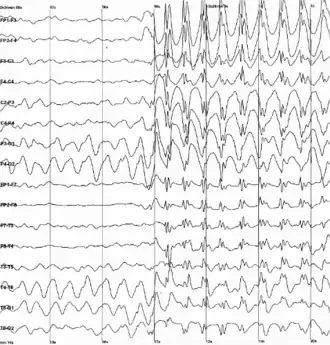

Electroencefalografía (3 Hz) de un niño al momento de una crisis epiléptica. | ||

Para diagnosticar la epilepsia se requiere conocer los antecedentes personales y familiares y, por lo general, se corrobora con un electroencefalograma (EEG). También forman parte del diagnóstico estudios de imagenología, mientras que se reservan los procedimientos diagnósticos más especializados para casos muy puntuales. El tratamiento consiste en la administración de medicamentos anticonvulsivos. En los casos refractarios (es decir, que no responden a estos tratamientos, sobre todo en los que se presentan series de convulsiones, y se pone por ello en peligro la vida), se apela a otros métodos, entre los cuales se incluye la cirugía.[cita requerida] La epilepsia causa múltiples efectos en la vida cotidiana del paciente, de manera que el tratamiento debe incluir el abordaje de estas consecuencias.

Cada tipo de epilepsia tiene diferentes manifestaciones que se determinan a través del tipo de crisis epiléptica, así como a través de la etiología, del curso de la enfermedad, de su pronóstico (desenlace probable de la enfermedad) y por último a través de un diagnóstico EEG (“curva de corriente en el cerebro”). El estudio del electroencefalograma no siempre informa que haya indicios de epilepsia porque muchas veces algunos cambios eléctricos se producen en zonas tan profundas dentro del cerebro que el electroencefalograma no los puede detectar. Igualmente hay que acotar que las descargas sub-clínicas no solo se generan en niños con epilepsia, sino también en aquellos que no la presentan.[9] Todos estos factores pueden ser muy diversos, según cada una de las diferentes formas de la epilepsia.

Las pruebas diagnósticas fundamentales en las personas con epilepsia son el electroencefalograma (EEG), que es de mayor utilidad cuando se realiza con una duración mayor a 6 horas,[29] la resonancia magnética de cerebro y los estudios genéticos.[30] Ambos deben ser repetidos en la evolución en algunas ocasiones para observar la evolución o confirmar la causa o el síndrome epiléptico, o incluso para tomar decisiones de tratamiento.[31]